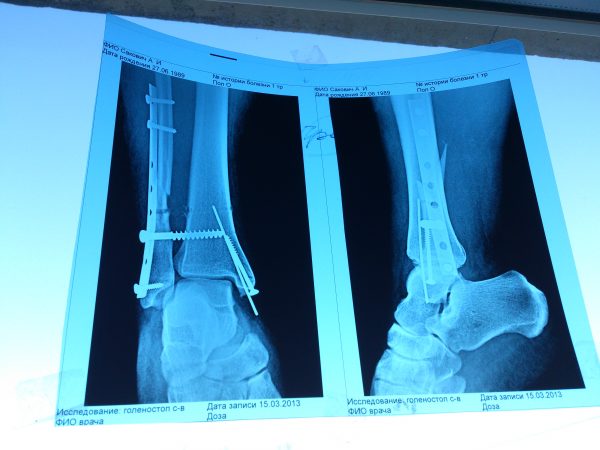

Когда я пришел на прием, оказалось, что все было плохо: переломы не срослись, нога распухла и почернела. Осмотрев ногу и сделанные только что снимки, врач сказал, что переломы не срослись, и состояние мое таково «что плохо сказать – это ничего не сказать». Если срочно не сделать операцию, мне грозит ампутация ноги.

Буквально неделю назад другие врачи заверяли меня, что скоро я буду играть в футбол, и от слов травматолога у меня потемнело в глазах. Единственным местом, где делали операции в таких сложных случаях, был Московский Институт травматологии имени Чаклина.